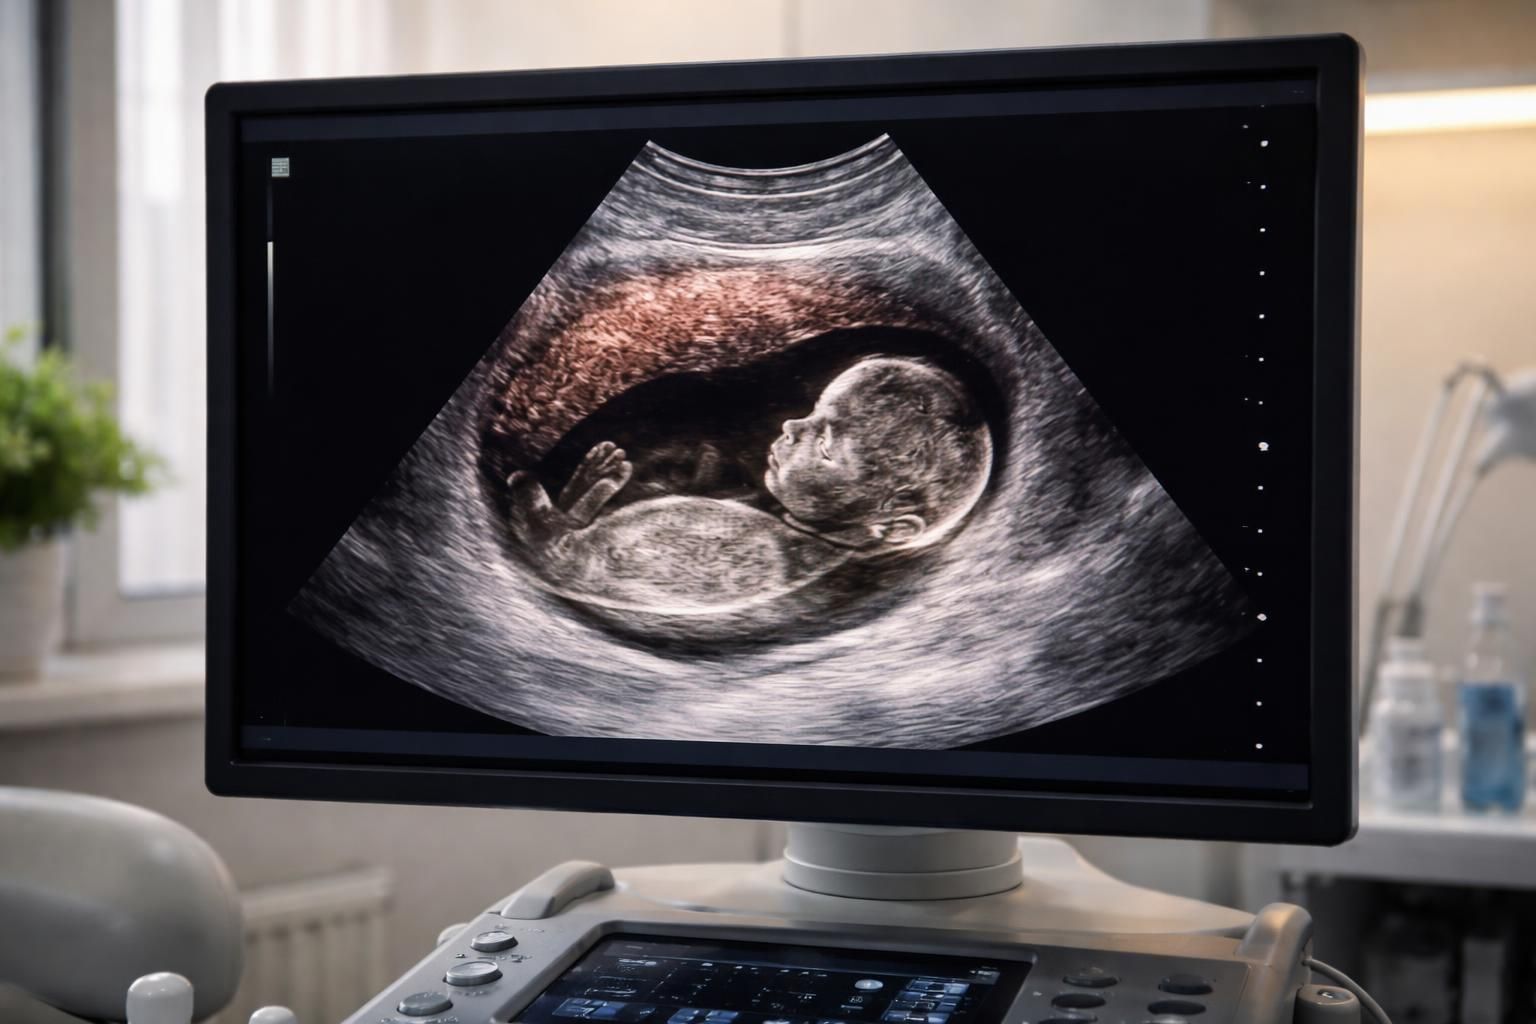

C’est la méthode la plus courante utilisée après le premier trimestre. Elle permet de visualiser le fœtus et le placenta dans le ventre de la mère. L’échographiste utilise une sonde placée sur l’abdomen pour envoyer des ondes sonores qui renvoient des images. Le placenta apparaît généralement en gris, plus homogène que d’autres structures comme les os qui sont visibles en blanc. Cela facilite l’identification visuelle sur l’écran de l’échographe.

Interpréter les images obtenues lors d’une échographie peut sembler complexe. Toutefois, il existe des codes de couleur et des symboles qui aident à identifier les différentes structures, y compris le placenta. Dans ce contexte, il est utile de savoir que le noir indique des liquides, alors que les tonalités de gris et de blanc correspondent à des tissus plus denses, comme les os.

Le noir sur une échographie représente généralement le liquide amniotique, tandis que le placenta, comme d’autres tissus mous, apparaît en nuances de gris. Les os, quant à eux, sont souvent présentés en blanc en raison de leur densité. Cette palette de couleurs est essentielle pour identifier les différentes structures lors de l’examen.